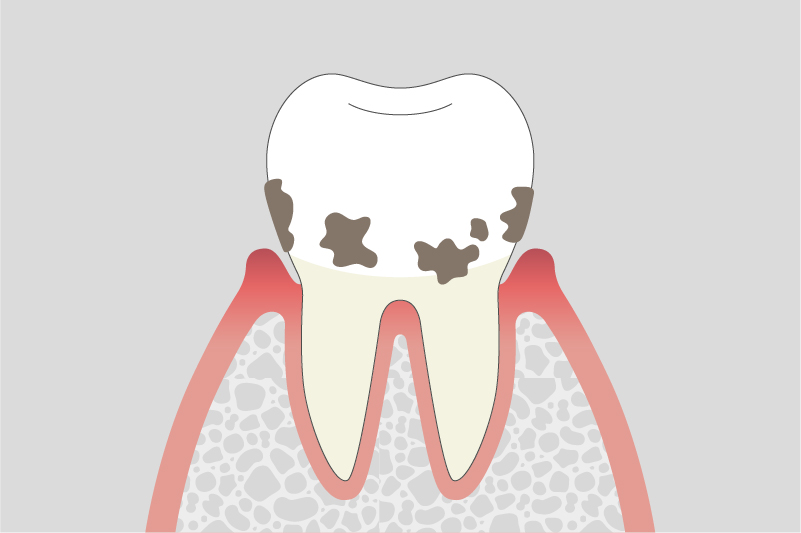

歯周病は、自覚症状が少ないまま進行することが多く、気づいた時には症状が進んでいる場合もございます。歯周病の進行を食い止め、大切な歯を健康に保ち続けるために、当院がどのように歯周病治療に取り組んでいるのかをご紹介いたします。

歯周病は、一度かかってしまうと完全に元に戻るのが難しい、生活習慣に関わる慢性的な病気です。そのため、一時的に治療をして終わりではなく、病気の進行を抑え、今の良い状態を長く保っていくことが何よりも大切になります。

1つでも当てはまったら、歯周病のサインかもしれません。

歯茎が腫れて出血することがある

口臭が気になり始めた

歯がぐらつく感じがする

冷たいものが歯茎にしみることがある

歯茎が下がってきて、歯が長く見えるようになった